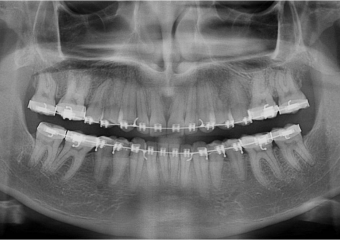

Raio X após cirurgia